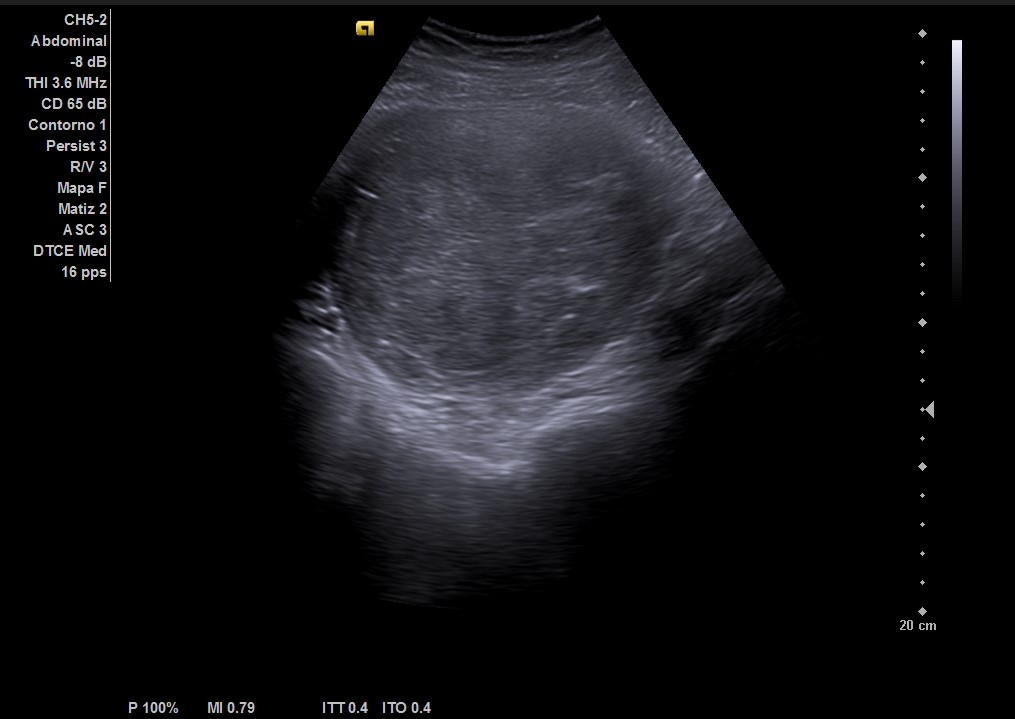

Ecografía abdominal: masa heterogénea de 10 x 10 cm dependiente de útero con vascularización periférica. No se observa la vejiga al estar repleccionada y desplazada por dicha masa. Se vuelve a hacer ecografía con vejiga llena y se observa cómo deforma la pared por efecto masa. Vejiga sin litiasis en su interior, no globo vesical.

Metrorragia secundaria a mioma uterino de gran tamaño.

La paciente es valorada en consulta de patología ginecológica. Le realizan una ecografía abdominal y transvaginal que describe: útero de unos 13 cm de histerectomía. Presenta varios miomas intramurales, destacando uno en cara posterior de 110 x 102 mm que parece contactar con cavidad endometrial sin desplazarla.